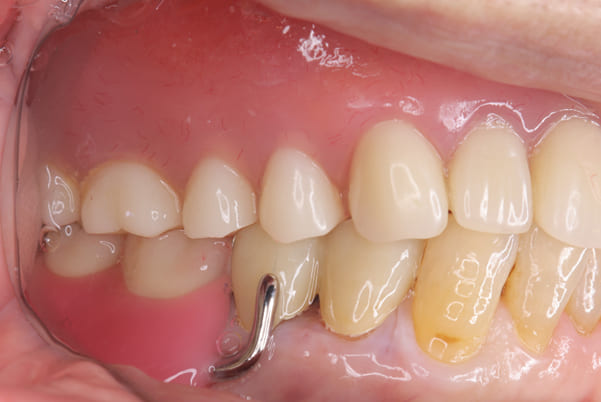

作製した入れ歯は、お食事の際に入れ歯の沈み込みを予防するため、適切なストッパーを付与することで、入れ歯は沈み込まなくなり、お痛みは消失しました。

右下のバネの位置は後ろに、左下のバネは見えづらい形態のバネを用いる設計とすることで笑った際にバネが見えないようになり、気にされることはなくなられました。

治療前後の口元の比較

こちらは、口を少し開いた時の治療前と治療後の

口元です。

正面から見た時にクラスプが目立たないように、

歯ぐきになじむ素材にて入れ歯を製作し、痛くなく自然に馴染み快適に生活を送れるようになりました。